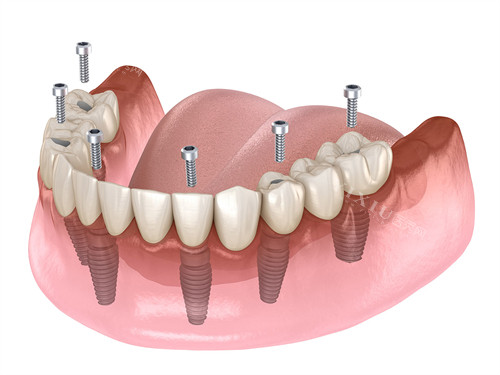

沃兰种植体的锥形主体设计能够很不错地贴合牙槽骨的形态,在植入时无需额外备孔,这对于骨量不足的患者来说是一个福音。就像一把钥匙能精密地插入锁孔一样,它可以直接植入牙槽骨,减少了手术的复杂性和对牙槽骨的损伤。

其颈部采用微螺纹与渐进螺纹结合的设计,大大增加了与骨组织的接触面积,从而提升了初期稳定性。特别是在牙槽骨骨壁较薄的情况下,这种设计能让种植体更加稳固地扎根在牙槽骨中。同时,内八角或 7° 内连接结构,有效地避免了螺丝松动的问题,确保了种植体在长期使用过程中的稳定性。

沃兰种植体提供了 IT、IU、Oneplant 等多个系列,每个系列又有不同的型号可供选择,直径从 3.6mm 至 5.5mm 以上,几乎覆盖了前牙、磨牙、尖牙等全口位点。例如,IU 3.6mm 型号适合上颌侧切牙或下颌前牙区;IU 4.5mm 型号适配前磨牙区;IU 5.5mm 型号则可用于磨牙及骨量充足的区域。这种多样化的选择,能够满足不同患者的个性化需求,无论是单颗牙缺失、多颗牙缺失,还是全口牙缺失,都能找到合适的解决方案。